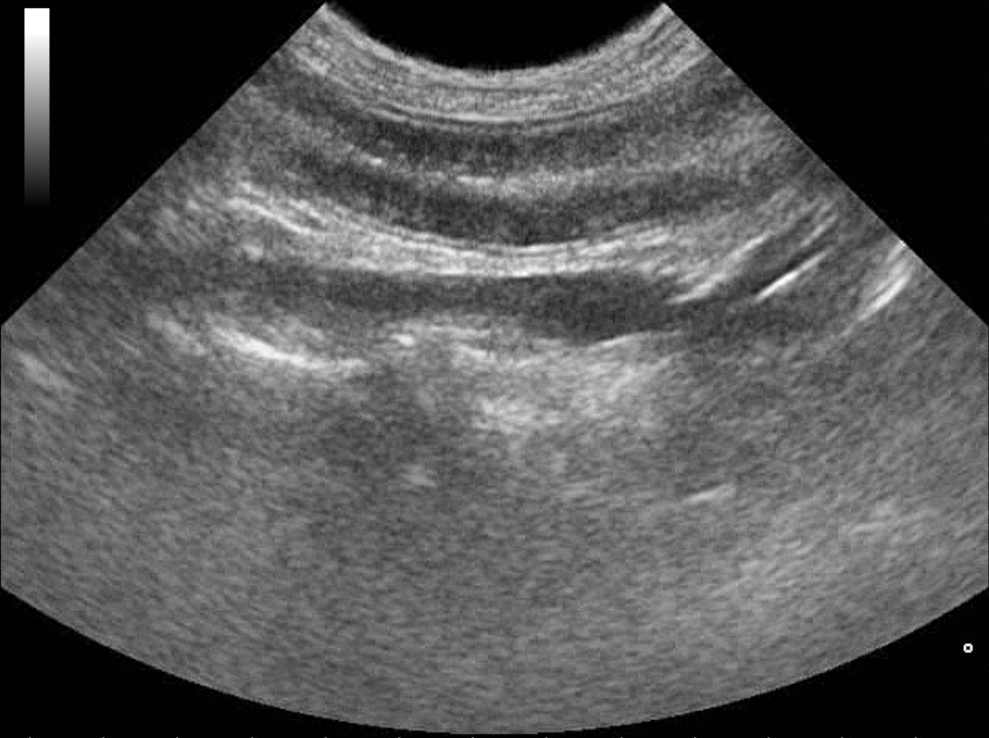

Webinář zaměřen na klinicky orientovanou sonografii gastrointestinálního traktu, se zaměřením na patologické nálezy, které mají přímý dopad na další diagnostický a terapeutický postup. Čeká na vás více než 50 komentovaných videosmyček z reálných klinických případů.